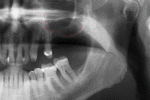

Success or failure of implants depends on the health of the person receiving it, drugs which affect the chances of osseointegration and the health of the tissues in the mouth. The amount of stress that will be put on the implant and fixture during normal function is also evaluated. Planning the position and number of implants is key to the long-term health of the prosthetic since biomechanical forces created during chewing can be significant. The position of implants is determined by the position and angle of adjacent teeth, lab simulations or by using computed tomography with CAD/CAM simulations and surgical guides called stents. The prerequisites to long-term success of osseointegrated dental implants are healthy bone and gingiva. Since both can atrophy after tooth extraction, pre-prosthetic procedures such as sinus lifts or gingival grafts are sometimes required to recreate ideal bone and gingiva.

When a more exacting plan is needed beyond clinical judgment, the dentist will make an acrylic guide (called a stent) prior to surgery which guides optimal positioning of the implant. Increasingly, dentists opt to get a CT scan of the jaws and any existing dentures, then plan the surgery on CAD/CAM software. The stent can then be made using stereolithography following computerized planning of a case from the CT scan. The use of CT scanning in complex cases also helps the surgeon identify and avoid vital structures such as the inferior alveolar nerve and the sinus.[17][18](p1199)

Placement of dental implants is a surgical procedure and carries the normal risks of surgery including infection, excessive bleeding and necrosis of the flap of tissue around the implant. Nearby anatomic structures, such as the inferior alveolar nerve, the maxillary sinus and blood vessels, can also be injured when the osteotomy is created or the implant placed.[34] Even when the lining of the maxillary sinus is perforated by an implant, long term sinusitis is rare.[35] An inability to place the implant in bone to provide stability of the implant (referred to as primary stability of the implant) increases the risk of failure to osseointegration.[14](p68)